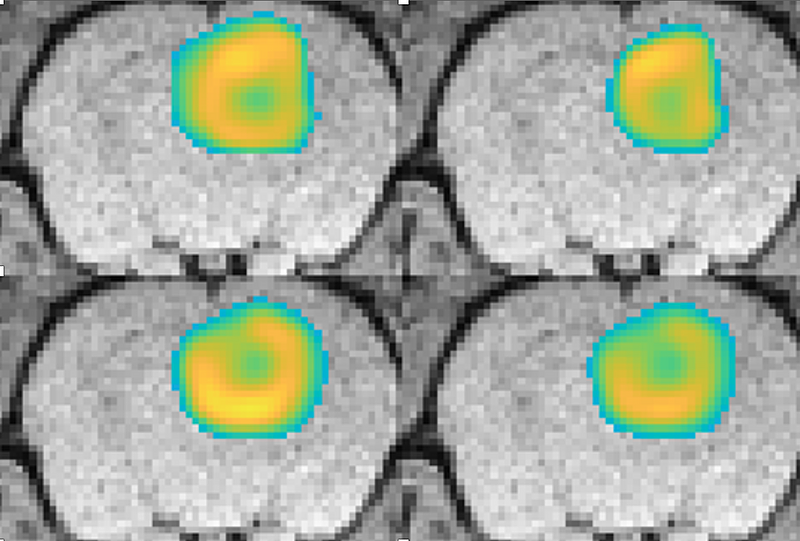

Image-driven models of tumor growth in the pre-clinical setting

Bayesian Inference of Tissue Heterogeneity for Individualized Prediction of Glioma Growth

Modeling of Glioma Growth With Mass Effect by Longitudinal Magnetic Resonance Imaging

Towards an Image-Informed Mathematical Model of In Vivo Response to Fractionated Radiation Therapy

Calibrating a Predictive Model of Tumor Growth and Angiogenesis with Quantitative MRI

Mechanically Coupled Reaction-Diffusion Model to Predict Glioma Growth: Methodological Details.